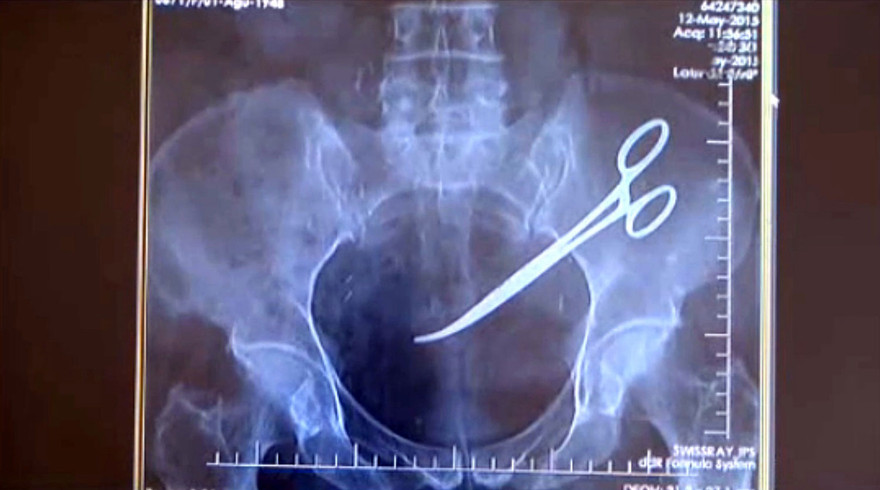

Năm năm sau, vào đầu tháng 12/2015, do quá đau ở dạ dày và bụng, bà Hanim quyết định tìm đến một bệnh viện khác để thăm khám. Các bác sỹ tại đây đã không thể tin nổi vào mắt mình khi cầm trên tay hình ảnh chụp X-Quang của bà. Theo đó, toàn bộ phần ổ bụng của bà bị viêm nhiễm nặng do có một "dị vật".

Sau ca mổ vào trung tuần tháng 11 vừa qua, "dị vật" được xác định là một chiếc kéo phẫu thuật. Bà Hanim cho rằng trong ca mổ cách đây 5 năm, các bác sĩ đã bỏ quên chiếc kéo này trong ổ bụng của bệnh nhân.